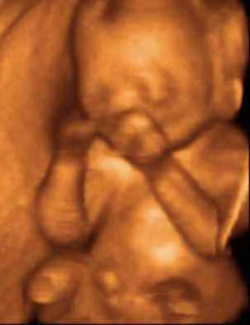

Antes y Después Antes y Después Boxeando Feto de 16 Semanas Feto de 21 Semanas

Boxeando